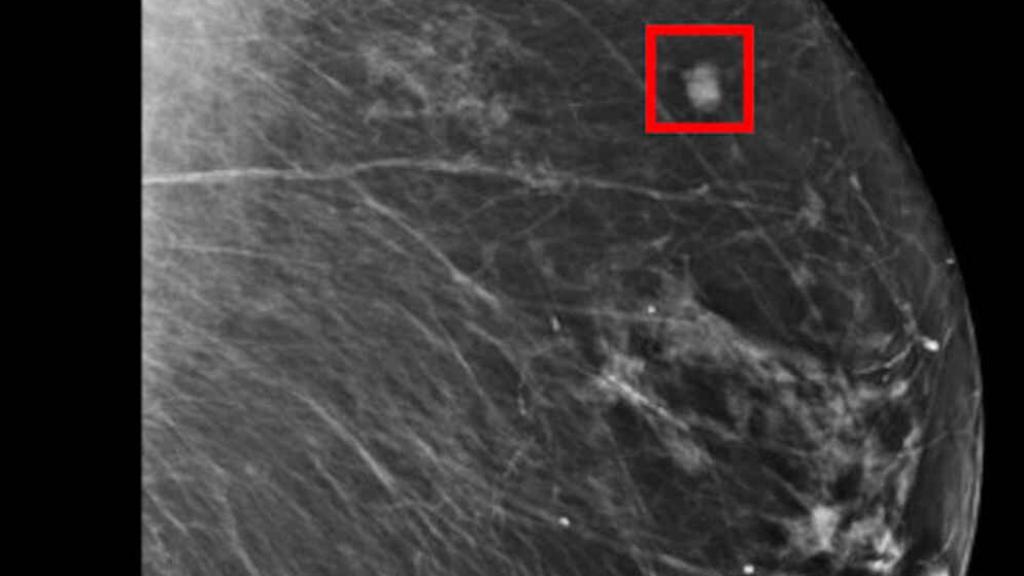

Imágenes de una mamografía.